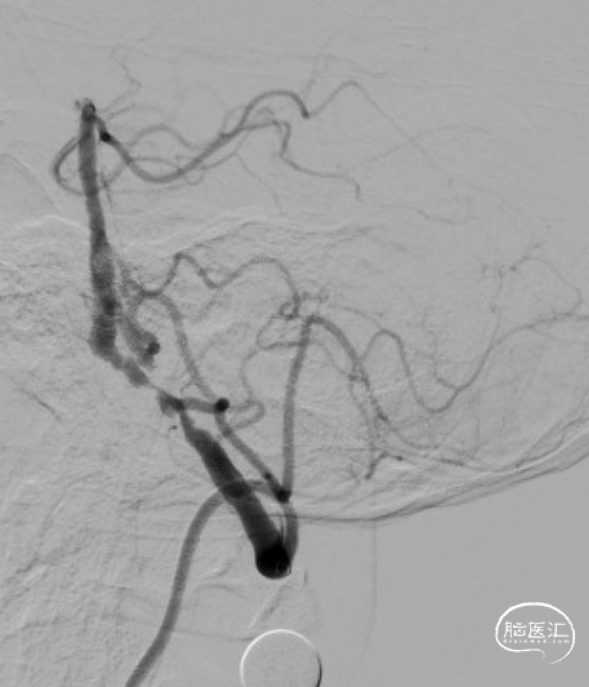

LSCA造影:LVA V2段闭塞。

RVA造影:RVA V4段重度狭窄。

DSA:RVA V4段重度狭窄90%。

术后造影:RV4段狭窄较前明显改善。